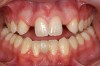

Figure 8 A lack of harmony in tooth size and position for an adult patient treated with cuspid substitution to replace the congenitally missing maxillary lateral incisors.

Figure 8